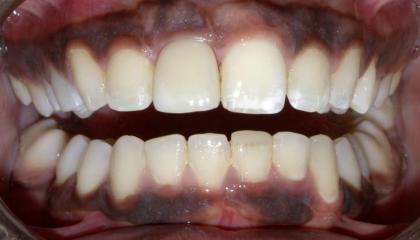

After